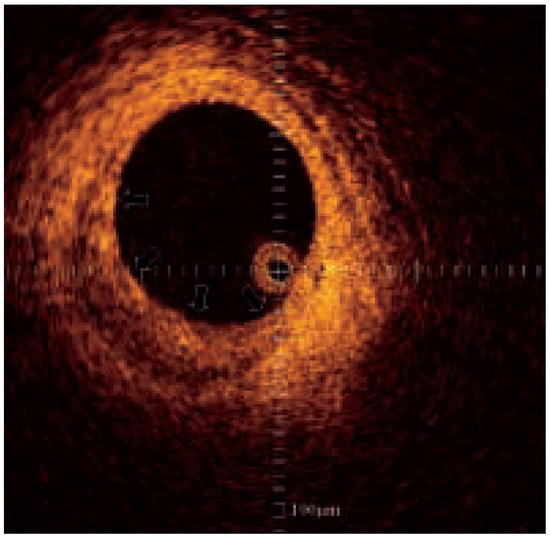

Optical coherence tomography